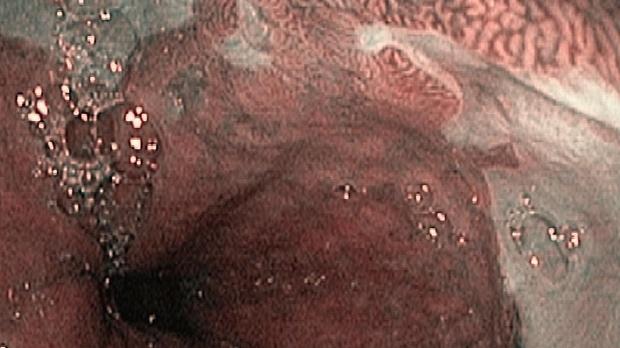

Появление ультратонких гастроскопов с высоким разрешением и технологией NBI (оптического узкоспектрального режима) компания OLYMPUS сделала возможной гастроскопию экспертного уровня под местной анестезией, без наркозных рисков.

Ультратонкие гастроскопы GIF-XP170N и GIF-XP190N с параметром оптики Close Focus, который позволяет приближаться к слизистой на минимальную глубину резкости до 2 мм, обеспечивают качество изображения, сопоставимое с аппаратами экспертного класса.

В Центре Экспертной Эндоскопии, г. Симферополь с июня 2018 с помощью этих эндоскопов выполнено более 1000 эндоскопических исследований, с полным соблюдением критериев качества ESGE. Среднее время исследования составило 14мин. 51с. Все исследования выполнялись с предварительной подготовкой желудка, применением водяной помпы и СО2-инсуффлятора, фото- и видеодокументацией.

Использование в ежедневной рутинной практике современных ультратонких эндоскопов высокого разрешения с технологией оптического узкоспектрального режима (NBI® OLYMPUS™) под местной анестезией позволило полностью обеспечить соответствие критериям качества выполнения эндоскопических исследований, определенным ESGE. Данный метод комфортен для пациента под местной анестезией, безопасен, является простой и удобной альтернативой ЭГДС под седацией, что особенно важно в амбулаторных условиях.